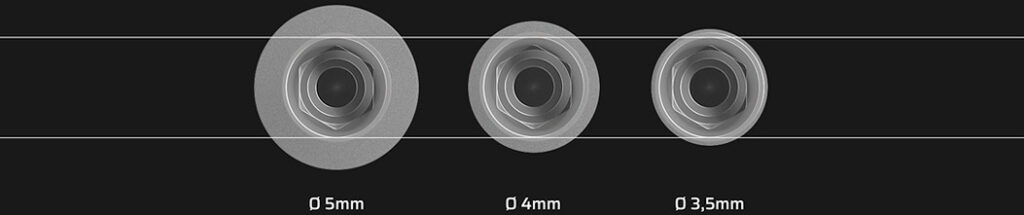

PLATAFORMA UNIFICADA

Todos los diámetros del implante comparten una única plataforma protésica, de tal forma que cualquier componente protésico es válido para todos los implantes de la gama, sean cuales sean sus dimensiones.

La conexión cónica indexada y la robustez del implante minimizan los micromovimientos y el gap entre componentes.